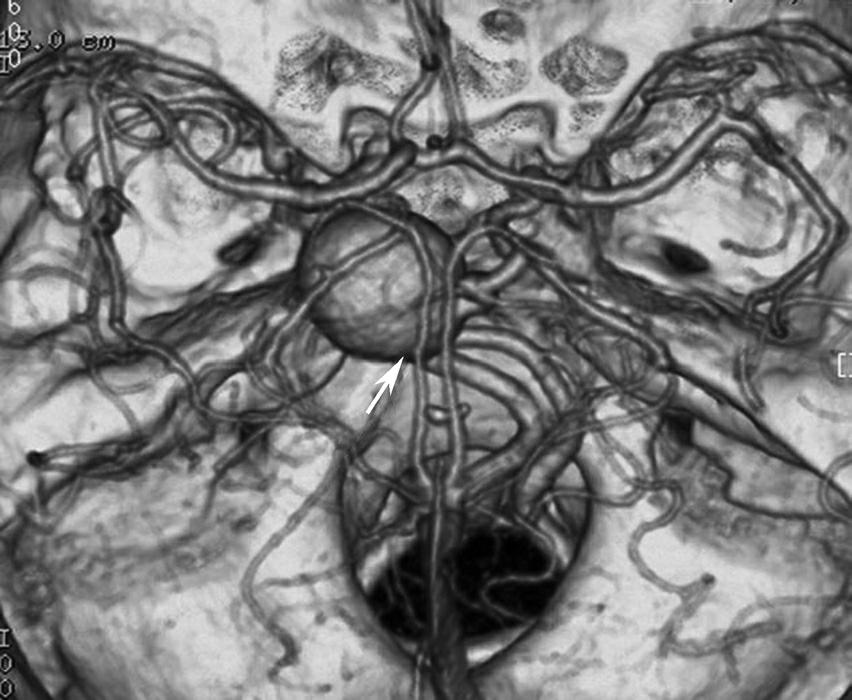

CT血管成像(CT angiography,CTA及CT venography,CTV)通过三维重建技术可显示颅内动静脉的走行、血管壁及血管周围等情况(图1-2-73~图1-2-75)。

图1-2-73 正常颅脑CTA

1.大脑前动脉;2.大脑中动脉;3.颈内动脉;4.大脑后动脉;5.基底动脉;6.椎动脉